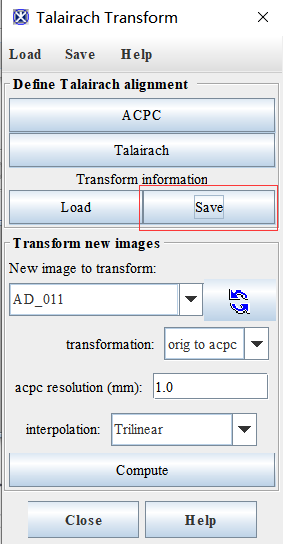

2、点击algorithm-brain tools-Talairash transformer

(6)保存变换信息:最后点击Apply,会显示ACPC结果(和原图),可以点击save保存变换信息

然后点击load,将之前的变换信息加载进去就会显示ACPC变换后的图片,点击New image to transformer栏的刷新按钮,然后选择AD_011_ACPC

然后将transformation改成acpc to orig,点击compute可以将变换后得图片和原图进行对比(不晓得有啥用)